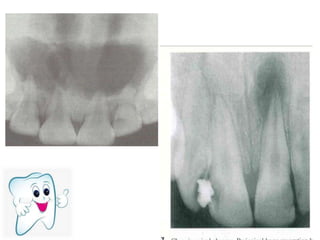

• It presents a well defined,spherical

shaped,radiolucent area in dentine which

usually continuous with the pulp

• Enlargement of root canal

• Original root canal outline is distored

Calcifications presenting as distinct intra-

chamber (or less often intra-canal)

radiopacities are known as pulp stones

The shape of the invagination varying from a

narrow and undilated fissure to a

tear-shaped loop pointing towards the main

body of the pulp

• It presentsa well defined,spherical shaped,radiolucent area in dentine which usually continuous with the pulp • Enlargement of root canal • Original root canal outline is distored

Calcifications presenting asdistinct intra- chamber (or less often intra-canal) radiopacities are known as pulp stones

The shape ofthe invagination varying from a narrow and undilated fissure to a tear-shaped loop pointing towards the main body of the pulp